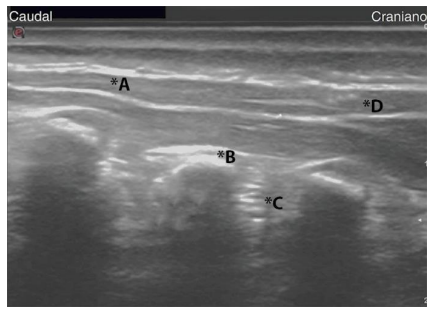

A figura a seguir representa a visão ultrassonográfica do plano do músculo eretor da espinha, na qual há indicação de diferentes pontos, representados pelas letras A, B, C e D.

O ponto correto de administração do anestésico local para realização do bloqueio do plano do eretor da espinha (ESP) está representado, na imagem, pela letra: